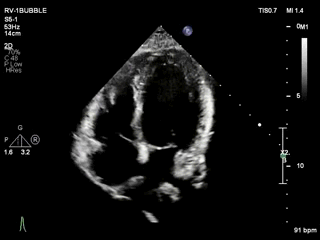

右心声学造影:

-

静息状态下右房显影后5个心动周期内左心房室显示大量造影剂微泡

Valsalva动作下右房显影后3个心动周期内左心房室显示大量造影剂微泡

静息状态

Valsalva动作